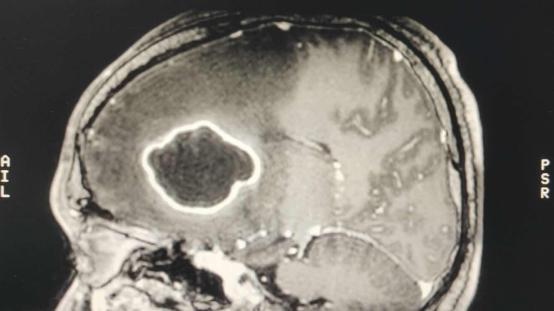

左额叶深部中线旁可见体积较大的脑脓肿,并周围大片脑水肿,颅内压明显增高,占位效应显著